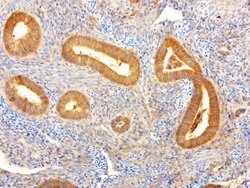

NME1 Mouse anti-Canine, Human, Rat, Clone: UMAB94, liquid, UltraMAB™

NME1 was identified because of its reduced mRNA transcript levels in highly metastatic cells. Nucleoside diphosphate kinase (NDK) exists as a hexamer composed of ′A′ (encoded by this gene) and ′B′ (encoded by NME2) isoforms. Mutations in the gene have been identified in aggressive neuroblastomas. Two transcript variants encoding different isoforms have been found for this gene. Co-transcription of this gene and the neighboring downstream gene (NME2) generates naturally-occurring transcripts (NME1-NME2), which encodes a fusion protein comprised of sequence sharing identity with each individual gene product.Specifications

| Immunocytochemistry, Immunofluorescence, Immunohistochemistry (Paraffin) | |